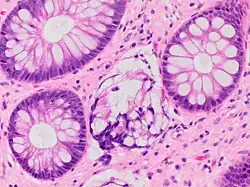

Micrograph showing intestinal crypt branching, a histopathological finding of chronic colitis. H&E stain.